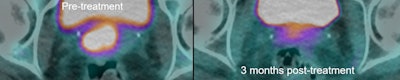

33-year-old LACC patient with stage 2B disease, node negative. MRI was performed 86 days after completion of conformal radiation therapy. Score grade 1 was recorded, indicating complete response. All images courtesy of Prof. Andy Scarsbrook. FDG-PET/CT in the same patient shows primary tumor, SUVmax 11.5. FDG-PET/CT scan performed 94 days after completion of CRT gave score of grade 4, indicating patient metabolic response.

FDG-PET/CT in the same patient shows primary tumor, SUVmax 11.5. FDG-PET/CT scan performed 94 days after completion of CRT gave score of grade 4, indicating patient metabolic response. MRI performed five months later showed local relapse. PET/CT confirmed this and showed no distant disease. Patient underwent salvage pelvic exenteration and was disease-free two years later.